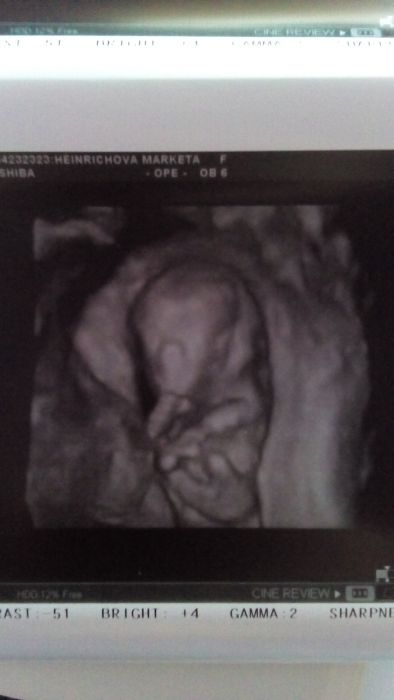

Ahoj holky,tak screening dopadl dobre.. Male nam povyrostlo a odpovida 12+3tt a TP se nam posunul o 3dny na 9.7. na dalsi utz jedeme 28.2. a za 14dni do poradny a budu vedet i vysledky z krve... Ze zacatku chrupkalo a pak se krasne hybalo. Hezky nam zamavalo a cumlalo si rucku a pohlavi je nam zatim asi neznamo... Je tam videt nehaky hrbolek,ale ani dr si nebyla jista jestli pindik nebo buchta a videli jsme i ve 4D,vypadalo tak nejak divne

Jéé Markéto, moc gratuluji k dobře vycházejícímu screeningu a k hezkým fotkám :-D. Tak to jsou fotky 3D, to u nás v Brně dávají plochou 2déčko a jen jednu a platilo se kolem 1500... ale třeba se za ty necelý tři roky polepšili, uvidím příští středu :-D. Ale to není podstatný, hlavně, že to dopadlo ok. Reakce mi je líto, ale důležité, že to klape doma a že se těšíte. Katko28, určitě u dobrých zpráv není brzo, jen obavy budou vždycky. Věřím na osud, stát se může něco v osmém týdnu, ale klidně i v dvacátém. A když to člověk řekne těm, kterým věří.... Mě teď přes Vánoce, kdy jsem dlabala od rána do večera, nebylo vůbec nevolno, tak ťukám na břicho ať se mi zase nějak ozve, ať vím, že tam je... jo je tam, už jsem musela vyměnit velikost S za M :-D.